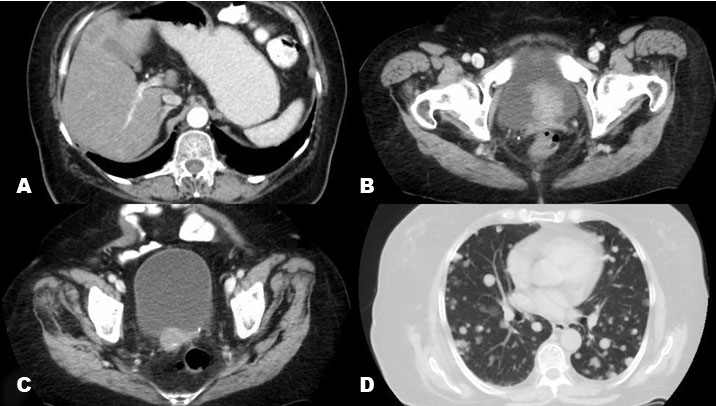

CT imaging confirmed widespread local and distant metastases in bladder, liver, and lung (Figure 3). Diffused distribution in multiple nodules were observed using posteroanterior and lateral chest teleradiography. Diffused pulmonary nodules suggested metastatic infiltration (Figure 4). The patient was weak and lost the ability to breathe, requiring a supply of oxygen. The patient also needed a urinary catheter and suffered from frequent constipation. In less than a month after performing the CT, she died (March 18, 2020), two days before the start of her chemotherapy regimen.

Figure 3: (A) The CT of the abdomen and pelvis showed liver lesions suggesting secondary metastasis of the tumor. (B) and (C) The CT scan showed nodule-like lesions in the uterine bed and in the vaginal canal with extensions to the bladder, suggesting residual lesion versus recurrence. (D) The CT also showed multiple pulmonary nodules were detected, suggesting secondary lesions.